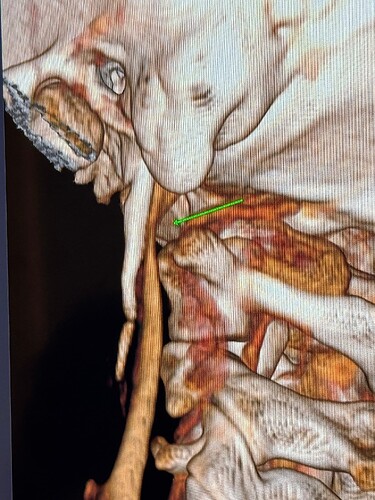

I have a cbct and CVA made wich shows elongated styloids and calcified stylohoids around 5 cm. Space left in neutral position between c1 is 3.5mm. Left IJV compression in laying position but there seems to be mainly some soft tissue compression there. So not due to compression of c1/styloid. The right is my dominant IJV.

They found a kinking carotis artery on the right at the c1 level.

Hi Rob & welcome! Looking at your CT, & obviously we’re not experts, I would estimate that your styloid & calcified ligament section is longer than 5 cm; on your left in the middle image it goes way past your C2 vertebra! We have found that the measurements from CTs are often wrong as it can be quite hard to measure accurately due to CT imaging being done in slices…

The IJVs do collapse naturally when flat, so it could be due to that, in your 3rd image it looks like the IJV is flattened higher up, so what would be right by the skull base. It could be like that naturally because of being flat for the CT, or it could be that it is being compressed where it emerges from the skull at the jugular foramen - if styloids are quite thick that is possible, & yours do look a little wide at the top… It looks like there could be something pinching the IJV between it & the styloid where you’ve marked too; we’ve had members who’ve had compression from an enlarged SCM muscle, the digastric muscle, omahyoid muscle, as well as other blood vessels & nerves… I’d guess where the compression is that the digastric muscle would be the most likely if it was a muscle, or maybe the stylohyoid muscle, although we don’t hear much about that one!

@Rob12345 - Welcome to our forum! I have nothing to add to what @Jules said, but did want to say WOW! You do have very long styloids. The “kink” in your ICA (internal carotid) isn’t really a kink more of a curve, but I can see based on the image, that it could be causing some slowed or backed up blood flow going into your brain. The IJV compression is curious as it appears to be more than the styloid causing the problem but clearly C1 seems not to be involved. I think Jules has made some logical assumptions regarding other possible compression culprits.